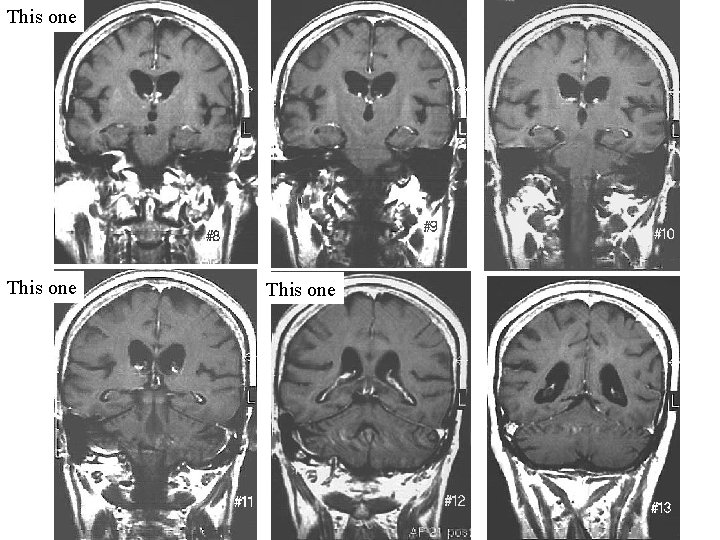

Not These Not these This one Not these

This one only

This one